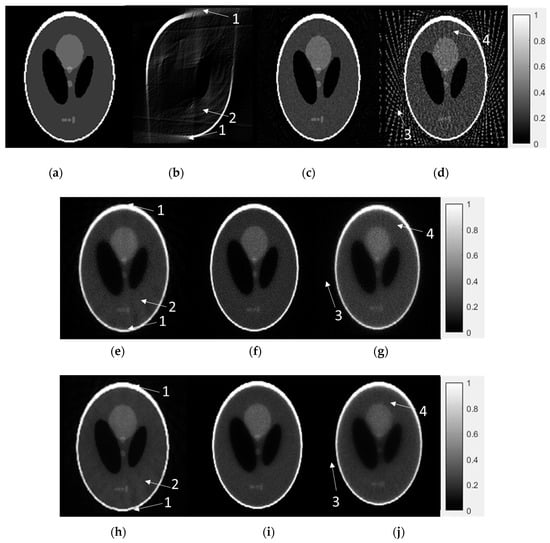

3.2. Numerical Reconstruction Evaluation

Here we use one Shepp-Logan phantom to evaluate the performance of three algorithms. Figure 7 is the ground truth value compared with the FDK, ASD-POCS and EM-TV algorithms. Here, the IR algorithms were proposed as stopping criteria in Equation (3). Each of the following cases included the LA, DSFC and LSFC modes. Four types of artifact patterns (unsmoothed-shape edge, curved-ripple pattern, streak-artifact and radiative-pattern) were used to evaluate the IQ. In Figure 7, the limitations of the FDK algorithm are apparent. Despite its compact sampling size and computation speed, the quality of the LA reconstruction is unacceptable due to insufficient information for only 90° of projection data. In terms of the LSFC data, although the sampling coverage is sufficient, the large sampling interval amplifies some streak artifacts outside of the object. While the FDK method generates artifacts, both the ASD-POCS and EM-TV algorithms reduce the appearance of artifacts to produce acceptable images. These data were reconstructed using the IR method because they lack adequate information for reconstruction using the conventional FDK method. Although some artifacts cannot be removed entirely, these IR methods can reconstruct an image where the IQ is similar to that of the ground truth image. These results provide evidence in support of implementation in a real-world system.

Figure 7.

Numerical results for 3D Shepp-Logan phantom: (a) True image. (b) FDK with LA mode (1°/projection with 90° coverage), (c) FDK with DSFC (1°/projection with 360° coverage) mode, (d) FDK with LSFC (5°/projection with 360° coverage) mode. (e) ASD-POCS + CE inpainting + IQ-based stopping criteria for LA mode, (f) DSFC and (g) LSFC mode. (h) EM-TV-based algorithm + CE inpainting + IQ-based stopping criteria for LA, (i) DSFC and (j) LSFC mode. Arrows point to the four types of artifact patterns: (1) unsmoothed shape edge (2) curved-ripple pattern (3) streak-artifact and (4) radiative-pattern.